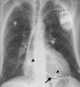

Pacemaker insertion

A cardiac pacemaker (or artificial pacemaker, so as not to be confused with the natural pacemaker of the heart), is a medical device that generates electrical impulses delivered by electrodes to cause the heart muscle chambers (the upper, or atria and/or the lower, or ventricles) to contract and therefore pump blood; by doing so this device replaces and/or regulates the function of the electrical conduction system of the heart. The primary purpose of a pacemaker is to maintain an adequate heart rate, either because the heart's natural pacemaker is not fast enough, or because there is a block in the heart's electrical conduction system. [Source: Wikipedia ]